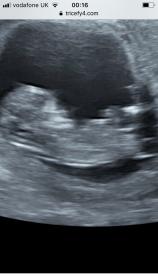

Hiya! I’d love some help with whether my baby has a nub in this pic and if so whether it looks like girl or boy?? Scan was at 12 weeks exactly. Thank you xx

I can see a white line ( not the one poking out but above that) and its kind of parallel to spine BUT id only say a slight G lean as not the best nub picture Congratulations on your baby :)

Sorry me again - I’ve done some more reading into nubs and I think I’m looking at the completely wrong thing. Can someone please explain where the actual nub is on those pics?? I’d be really grateful. I’ll post some more pics as well